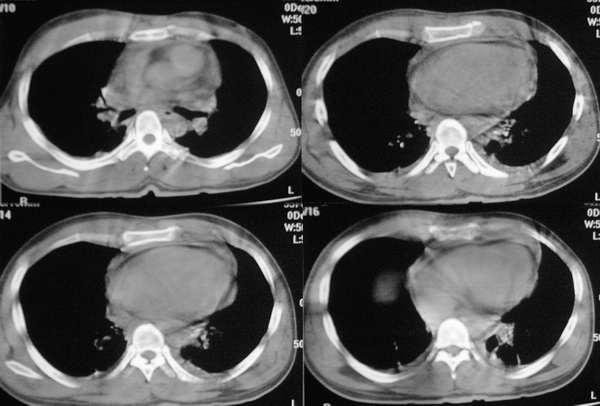

该病例认为心包积液>纵隔血肿可能,其理由有以下几点:

1、该病例ct平扫见上纵隔增宽,但见向内凹弧形影,而不是向外突张力增高影,试想如果上纵隔有积血,积血量大,那么纵隔内容量增多,压力大,且纵隔线应该向外突,而该病例是向内凹的。

3、主动脉弓以下大血管及心脏周围见环形低密度影,而主动脉弓以上大血管周边未见环形影。

5、复习了解剖后,可以看出该病例的低密度影,始终围绕大血管及心脏,而大血管以血管未见明显低密度影。

6、x线平片诊断外伤性纵隔积血主要与心包积液相鉴别:立、卧位摄片时纵隔形态变化有参考价值,前者立、卧位时上纵隔变化较大,而后者上纵隔增宽主要是腔静脉回流受阻所致,随体位变化不大。

7、纵隔血肿与心包积液ct书上的鉴别诊断,目前没有查到,如果那位战友有这方面的资料请上传,在此谢谢了!

看了12,13楼的分析受益非浅,肺窗右肺上叶不张.左下肺挫伤.